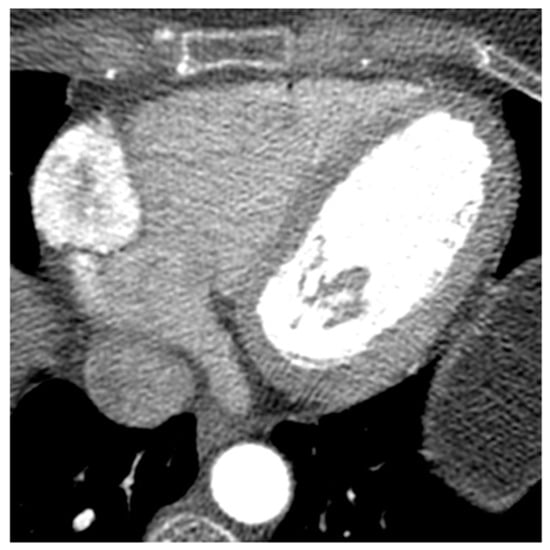

| Mitral annular calcification | Old patients | annular fibrous ring of the mitral valve | Asymptomatic | Calcifications, mitral valve | Hyperechoic | Calcific mass | Hypo T1w, hypo T2w, peripheral rim enhancement |

| Caseous degeneration of mitral annular calcification | Old patients | annular fibrous ring of the left atrio-ventricular valve | Asymptomatic | Calcifications, mitral valve | hyperechoic | Calcifications within and around the mass | Mildly hyper T1w, mildly hyper T2w, peripheral rim enhancement sometimes with central enhancement |